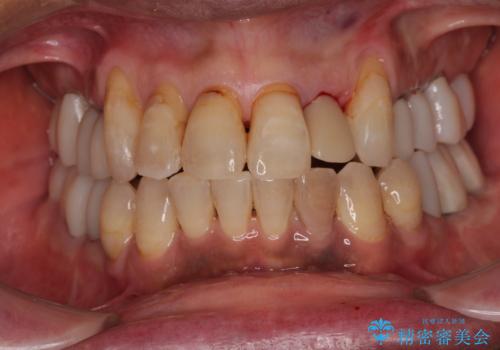

前歯のインプラント治療は、従来の抜歯から数ヶ月待機する手法では、骨造成や歯肉移植など付随の処置が多く必要となり、費用、期間、身体的負担のいずれもが多大となります。

抜歯時にインプラントを埋入することでそれらの負担を大きく軽減させることが可能です。